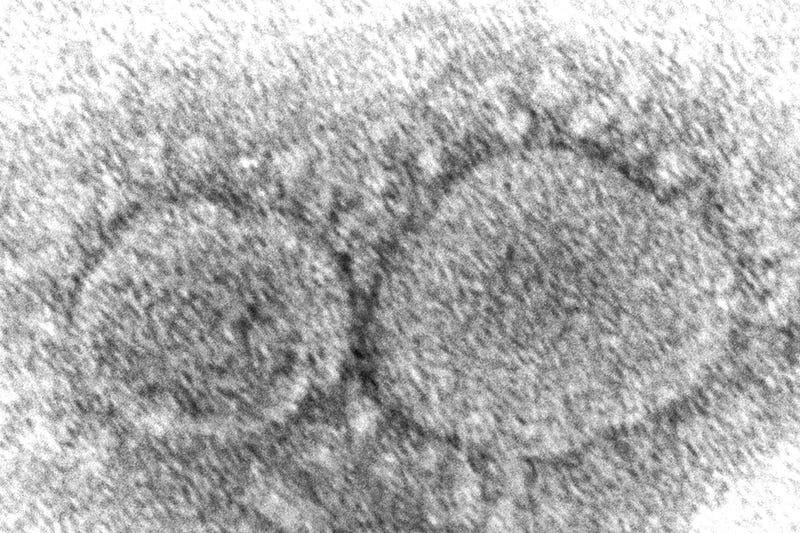

This 2020 electron microscope image made available by the Centers for Disease Control and Prevention shows SARS-CoV-2 virus particles which cause COVID-19. According to research released in 2021, evidence is mounting that having COVID-19 may not protect against getting infected again with some of the new variants. People also can get second infections with earlier versions of the coronavirus if they mounted a weak defense the first time. Photo credit Hannah A. Bullock, Azaibi Tamin/CDC via AP

Featured Image Photo Credit: Hannah A. Bullock, Azaibi Tamin/CDC via AP